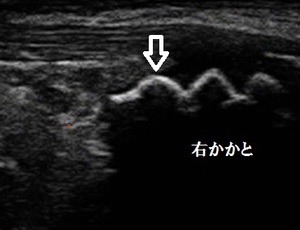

右踵 超音波長軸像 左健側 左踵 4週経過画像

川越市若葉 小学4年男子。 足、踵(かかと)の痛み、シーバー病。

歩いていました。超音波検査を実施したところ、右踵(かかと)のアキレス腱付着部の軟骨の表面が

左に比べて山模様が崩れ、不正になっている様子が認められました(左画像の赤丸の囲み)。

治療が4週経過した時に確認した超音波画像では、ガタガタになっていた右踵がきれいな骨のラインを

描出していることが確認させました(右画像矢印)。痛みも全くなくなり、現在は卓球のクラブチームの

練習も思い切ってできています。